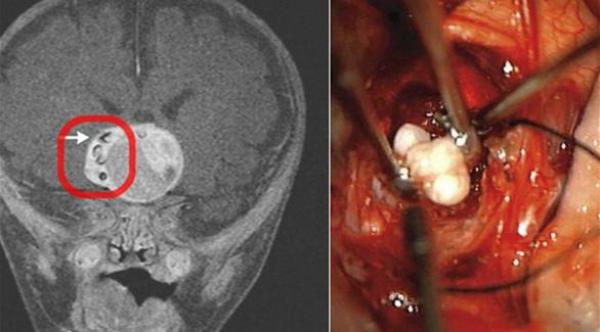

وأفادت التقارير الطبية إنه تم اكتشاف الورم بالقرب من الغدة النخامية للرضيع بعد أن كشفت اختبارات عن نمو غير طبيعي لرأسه، بحسب مديكال دايلي نيوز.

وقال جراح الأعصاب الذي أجرى العملية نارلين بيتي، إنه لم يسمع من قبل عن "أسنان" تنمو داخل ورم دماغي وإن تشخيص هذه الحالة كان تحدياً طبياً كبيراً لافتاً إلى أنها أرسلت إلى المختبرات لتخضع لمزيد من الفحوصات، إذ من الممكن أن تساعد في الأبحاث الطبية المستقبلية.

وإذ أفادت التقارير أنها الحالة الأولى التي يتم فيها اكتشاف أسنان في ورم دماغي، أكد بيتي أنه سبق العثور على سنين مكتملي النمو داخل ورم في عين امرأة هندية تبلغ من العمر 23 عاماً. وفي عام 1979 عانى رجل يدعى دووغ بريتشار من آلام شديدة لعدة أسابيع في قدمه اليسرى، قبل أن يكتشف الأطباء وجود سن نما داخلها.